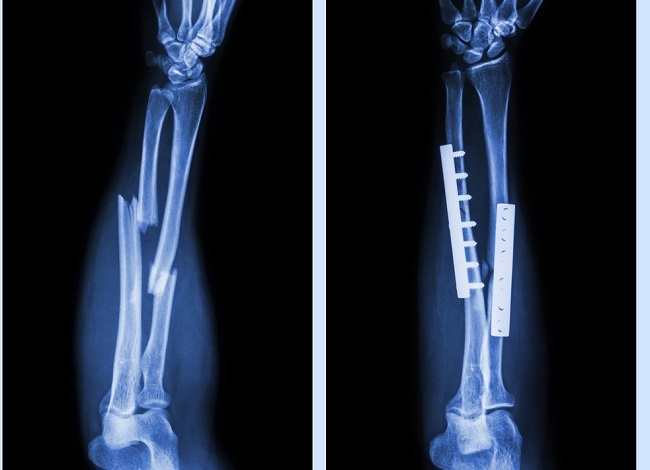

Jenis implan ortopedi lainnya adalah implan ortopedi sementara yang biasanya digunakan untuk stabilisasi fraktur. Implan ortopedi sementara, seperti plates and screws, wires, intramedullary nails, berfungsi untuk mempertahankan stabilitas setelah dilakukan reduksi pada fraktur. Implan jenis ini biasanya menggunakan material dengan bahan stainless steel atau titanium. Hal ini diperlukan agar tulang yang patah dapat mengalami penyambungan dengan baik. Setelah terjadi penyambungan tulang dengan sempurna, maka implan tersebut telah kehilangan fungsinya dan hanya menjadi benda asing dalam tubuh.

Dalam artikel ini, penulis mengkhususkan pembahasan mengenai implan ortopedi sementara, terutama dalam penggunaan plates dan screws atau biasa disebut plat logam untuk fiksasi fraktur.[1,2]

Setelah terjadi penyembuhan fraktur secara sempurna (fracture union) maka plat logam telah kehilangan fungsinya dan hanya menjadi benda asing dalam tubuh. Meski demikian, operasi pengangkatan plat logam merupakan tindakan yang invasif, dimana diperlukan pembuatan insisi lagi pada kulit dan juga pasien akan terpapar risiko bedah maupun anestesi. Hal ini menyebabkan masih banyak perdebatan mengenai apakah tindakan pengangkatan plat logam secara rutin diperlukan pasca penyembuhan fraktur apabila pasien tidak memiliki keluhan.